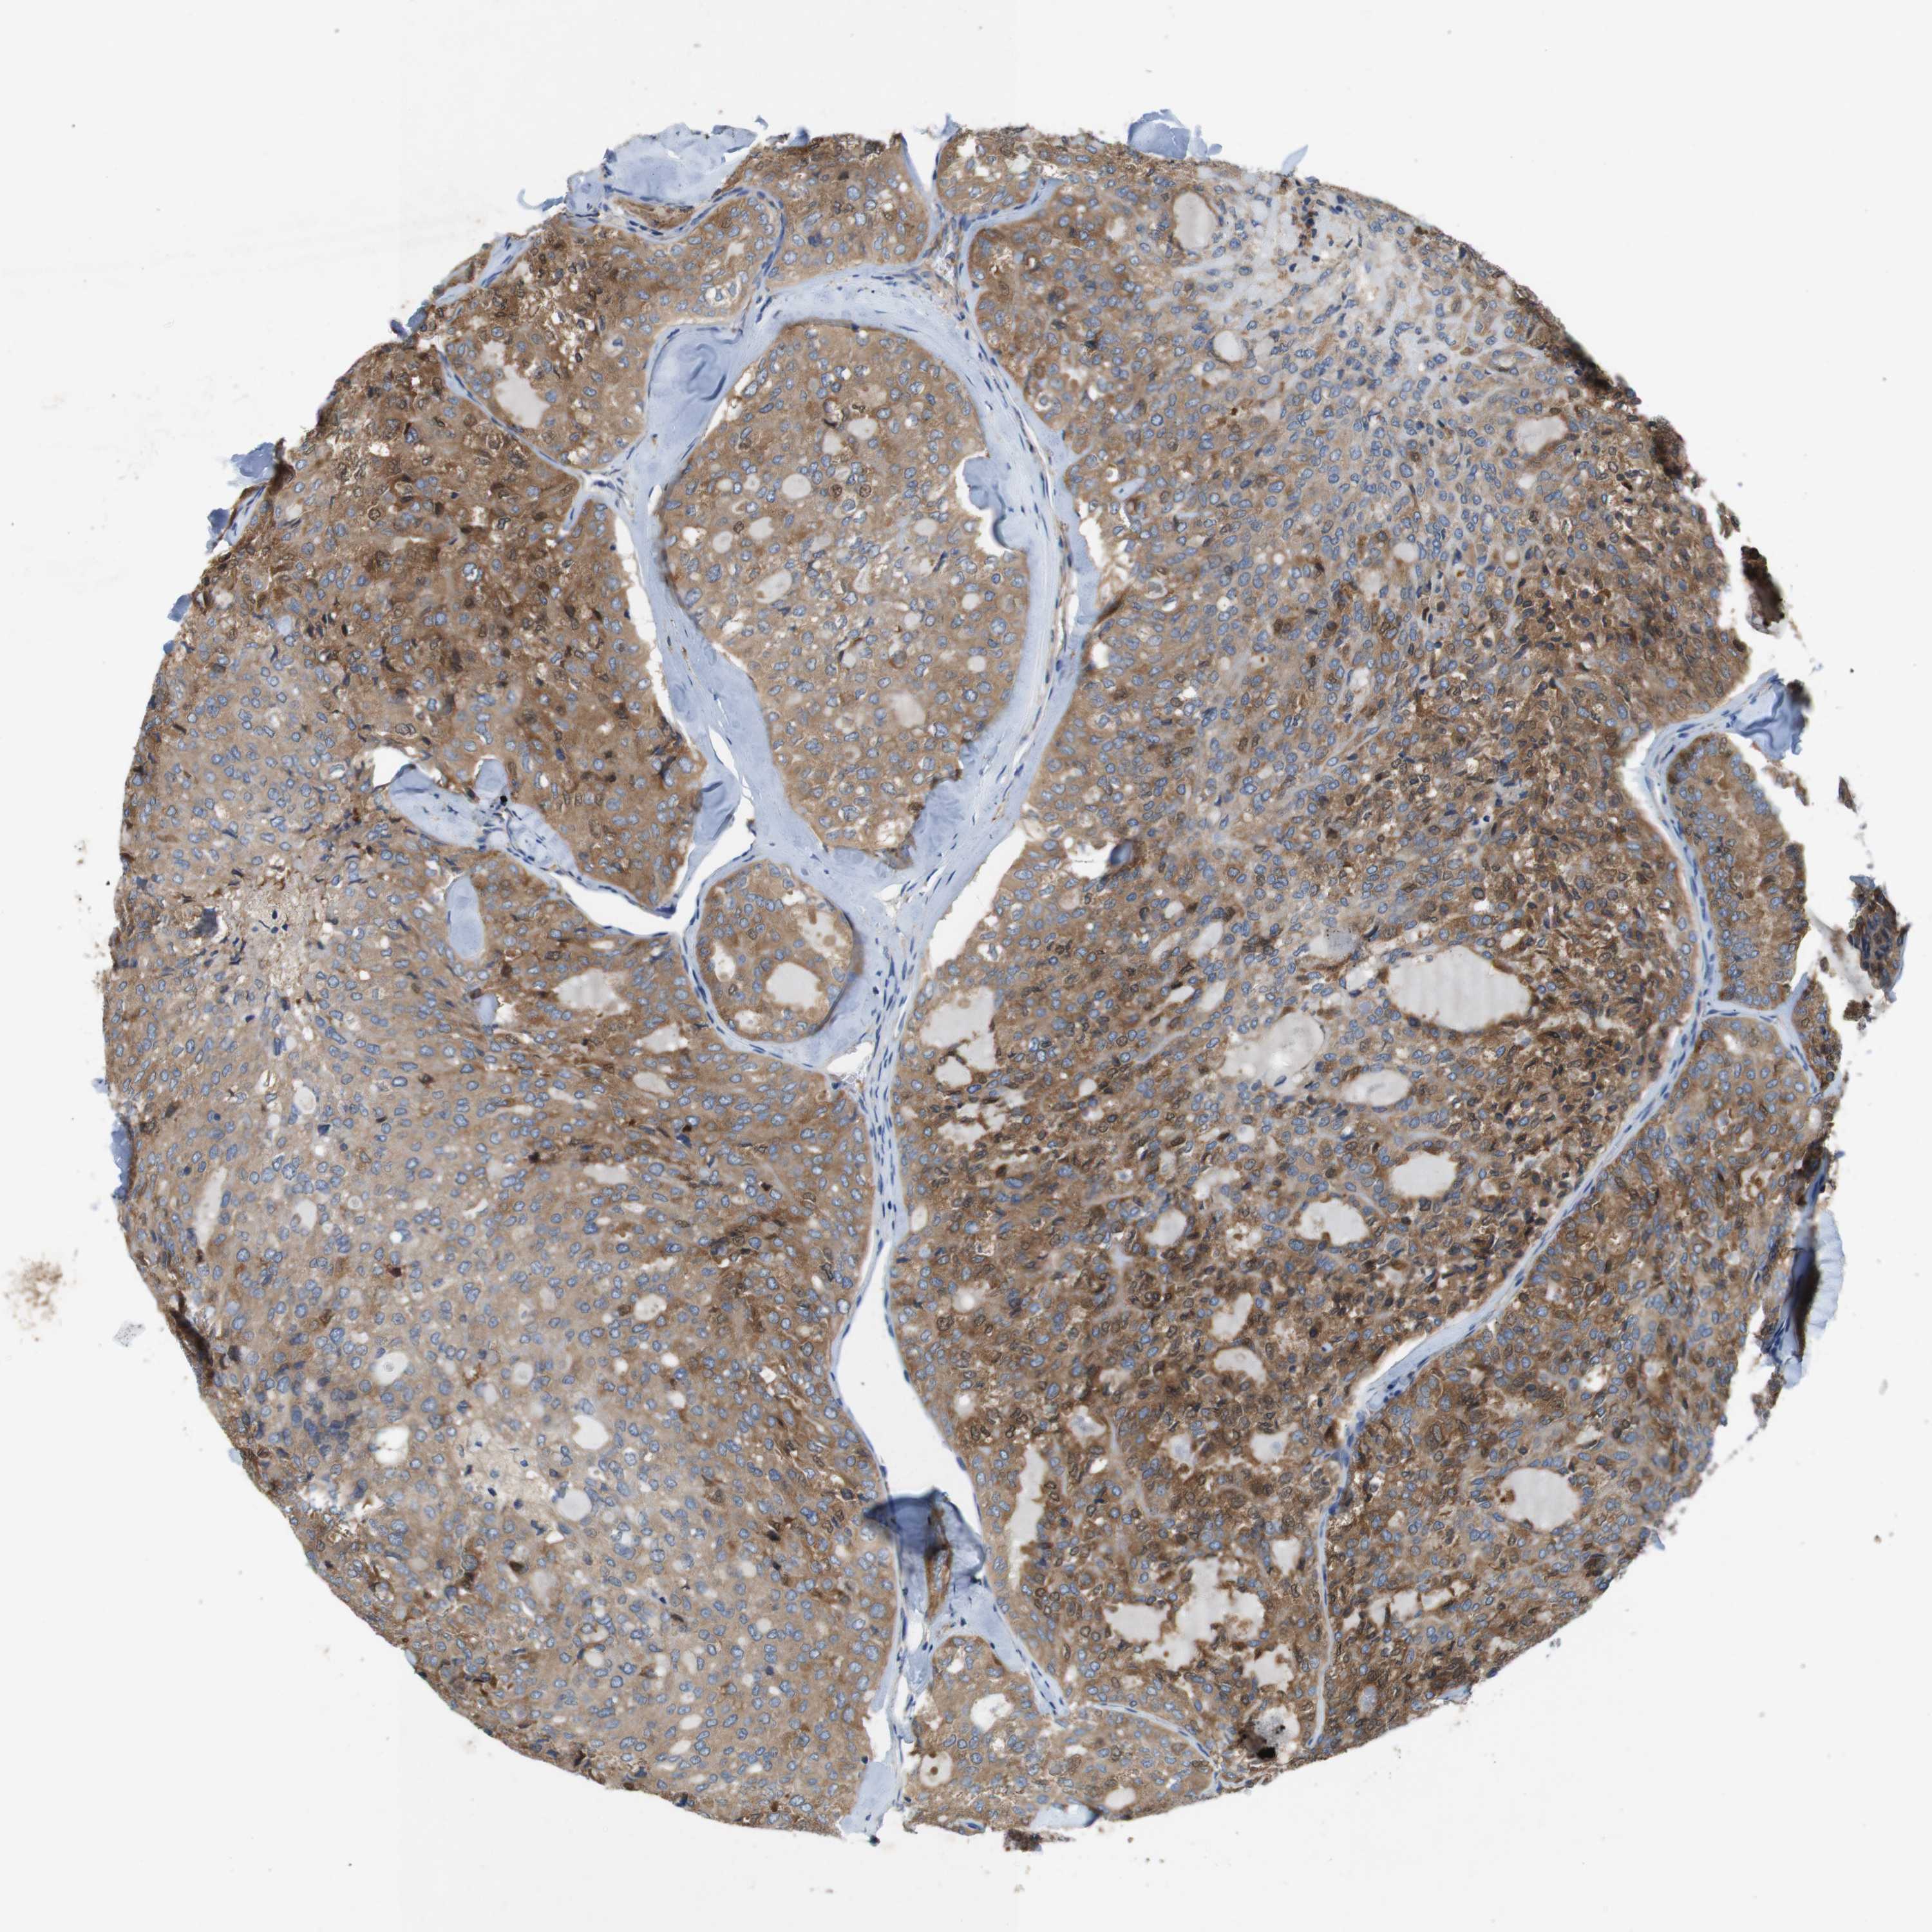

THYROID CANCER - Protein expressioni

A mouse-over function shows sample information and annotation data. Click on an image to view it in a full screen mode. Samples can be filtered based on level of antibody staining by selecting one or several of the following categories: high, medium, low and not detected. The assay and annotation is described here.

Note that samples used for immunohistochemistry by the Human Protein Atlas do not correspond to samples in the TCGA dataset.

Antibody stainingi

Antibody staining in the annotated cell types in the current human tissue is reported as not detected, low, medium, or high, based on conventional immunohistochemistry profiling in selected tissues. This score is based on the combination of the staining intensity and fraction of stained cells.

Each image is clickable and will lead to virtual microscopy that enables deeper exploration of all samples and also displays staining intensity scores, fraction scores and subcellular localization as well as patient and tissue information for each sample.

Antibody HPA034635

Antibody HPA069977

Antibody HPA071875

Antibody CAB009108

Staining

High

Medium

Low

Not detected

Intensity

Strong

Moderate

Weak

Negative

Quantity

>75%

75%-25%

<25%

None

Location

Nuclear

Cytoplasmic/membranous

Cytoplasmic/membranous,nuclear

Papillary adenocarcinoma, NOS

Follicular adenoma carcinoma, NOS